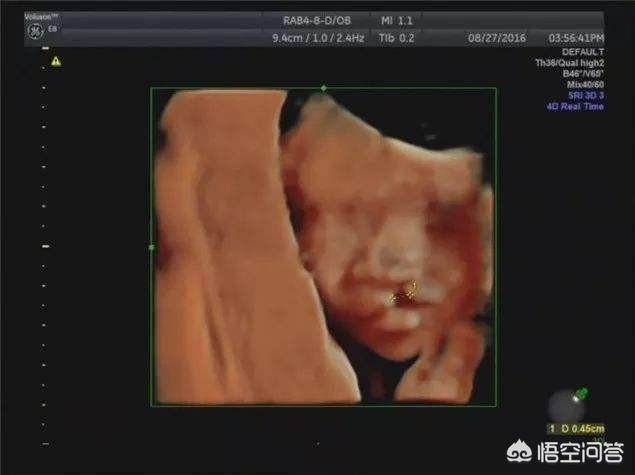

L'échographie 4D est une version améliorée de l'échographie b-scan, qui permet de détecter les malformations fœtales, les organes du visage et du corps du fœtus, les malformations des membres, telles que : fente labiale fœtale, syndactylie, quadruple cavité cardiaque, ectopie viscérale,...

Une échographie 4D pendant la grossesse permet de vérifier la présence de cardiopathies congénitales, d'hydrocéphalie, de fentes labiales et palatines, ainsi que le développement des membres du fœtus. L'échographie 4D permet également de voir l'image en mouvement du fœtus à l'intérieur du corps de la mère.

Communément appelé échographie 3D ou échographie 4D, il s'agit en fait d'un examen échographique visant à exclure la présence de maladies congénitales dans les différents systèmes et organes du fœtus.

L'échographie (échographie 4D) est un élément indispensable du test de grossesse. Elle est principalement chargée d'examiner la surface du corps du fœtus et divers organes pour y déceler des malformations. Par exemple : le cœur du fœtus, le cerveau, les reins et d'autres parties de la maladie.

De nombreuses réponses mentionnent l'échographie 4D, l'une des méthodes d'échographie les plus populaires de ces dernières années, qui permet de voir plus clairement l'image du fœtus, ce qui ajoute de la joie et du plaisir aux futures mères et aux futurs pères, ainsi que l'enregistrement de vidéos ou de photos à conserver en souvenir.